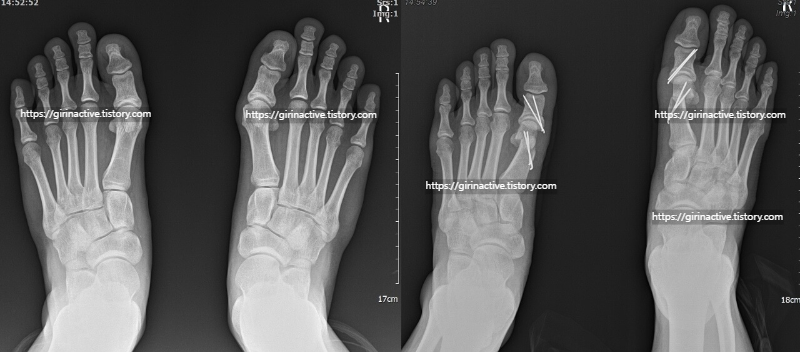

3. 사진 필터 없음 무지외반증 수술과 비복근 수술 후기

먼저 저는 2023년 1월 19일 목요일 오후 4시 30분에 수술을 들어갔습니다. 무지외반증 양발 수술과 비복근 수술 양쪽 종아리를 수술을 했습니다. (아킬레스건 = 종아리 근육)

👉최소 침술이 아닌 절개를 통해 무지외반증 수술을 하였고 뼈 제거, 휜 엄지발가락 철심으로 고정했습니다.

저는 왼쪽이 심한 상태가 아니고 오른쪽이 심한 상태였습니다. 육안으로 확인해도 엄지발가락 쪽인 왼쪽으로 많이 휘었고, 엄지발가락 밖에 부분은 뼈가 자라고 있는 부분을 제거했습니다.

수술 후 드레싱 할 때 제 발가락, 발등을 보았을 때 휜 부분이 고정이 되어서 만족한 수술이었습니다.

무지외반증은 위쪽 사진처럼 최소침습 수술법과 심한 분들은 저처럼 절개해서 교정 후 철심을 박는 경우가 있습니다. 제 경우는 심한 편이어서 나중에 저는 철심제거 수술까지 진행했습니다.